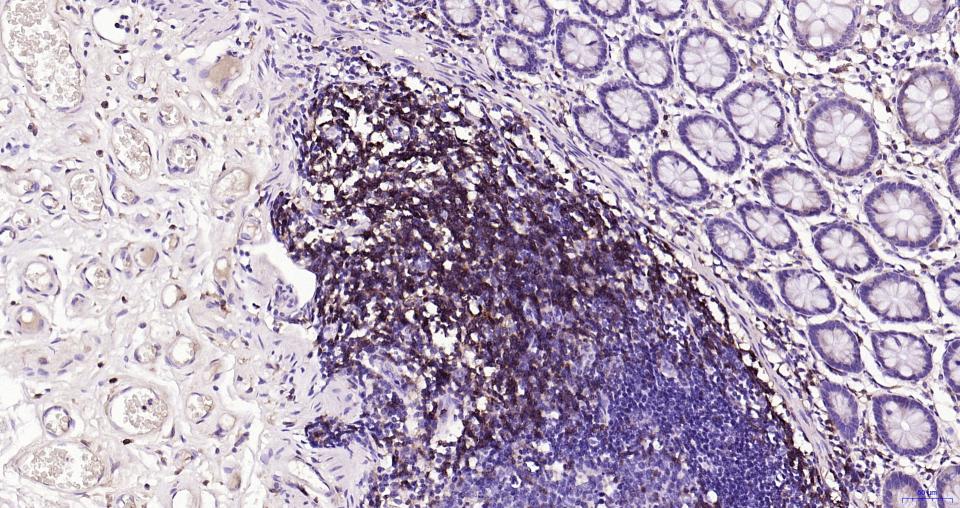

Paraformaldehyde-fixed, paraffin embedded Human Gastric Cancer; Antigen retrieval by boiling in sodium citrate buffer (pH6.0) for 15 min; Antibody incubation with CD4 Monoclonal Antibody, Unconjugated(bsm-52469R) at 1:200 overnight at 4°C, followed by conjugation to the bs-0295G-HRP and DAB (C-0010) staining.

Paraformaldehyde-fixed, paraffin embedded Human Spleen; Antigen retrieval by boiling in sodium citrate buffer (pH6.0) for 15 min; Antibody incubation with CD4 Monoclonal Antibody, Unconjugated(bsm-52469R) at 1:200 overnight at 4°C, followed by conjugation to the bs-0295G-HRP and DAB (C-0010) staining.

Paraformaldehyde-fixed, paraffin embedded Human Colon Cancer; Antigen retrieval by boiling in sodium citrate buffer (pH6.0) for 15 min; Antibody incubation with CD4 Monoclonal Antibody, Unconjugated(bsm-52469R) at 1:200 overnight at 4°C, followed by conjugation to the bs-0295G-HRP and DAB (C-0010) staining.

Paraformaldehyde-fixed, paraffin embedded Human Tonsil; Antigen retrieval by boiling in sodium citrate buffer (pH6.0) for 15 min; Antibody incubation with CD4 Monoclonal Antibody, Unconjugated(bsm-52469R) at 1:200 overnight at 4°C, followed by conjugation to the bs-0295G-HRP and DAB (C-0010) staining.

Paraformaldehyde-fixed, paraffin embedded Human Small Intestine; Antigen retrieval by boiling in sodium citrate buffer (pH6.0) for 15 min; Antibody incubation with CD4 Monoclonal Antibody, Unconjugated(bsm-52469R) at 1:200 overnight at 4°C, followed by conjugation to the SP Kit(Rabbit, SP-0023) and DAB (C-0010) staining.

Paraformaldehyde-fixed, paraffin embedded Human Colon; Antigen retrieval by boiling in sodium citrate buffer (pH6.0) for 15 min; Antibody incubation with CD4 Monoclonal Antibody, Unconjugated(bsm-52469R) at 1:200 overnight at 4°C, followed by conjugation to the SP Kit(Rabbit, SP-0023) and DAB (C-0010) staining.